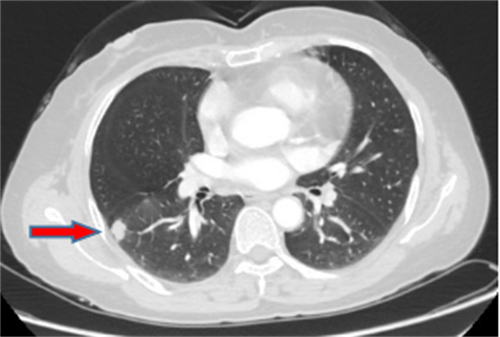

王女士,57岁,体检发现右下肺结节2月,术后病理诊断肺结节为肺隐球菌病。